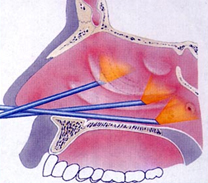

A képen jól látható az endoszkópos vizsgálat, amelynek során pontos képet kapunk az orrüreg és a melléküregek bemeneti nyílásainak állapotáról.

Az orrpolip műtét

Az orrpolip műtétek során az orvos az orrlyukakon keresztül bevezetett, speciális vékony optikán keresztül monitoron látja a műtéti területet és vékony, speciális célműszerekkel távolítja el a túlburjánzott nyálkahártyát.

Az alábbi animációs filmen megnézheti, mit lát az operáló orvos műtét közben.